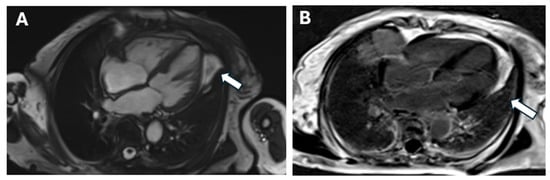

5. Clinical and Paraclinical Presentation